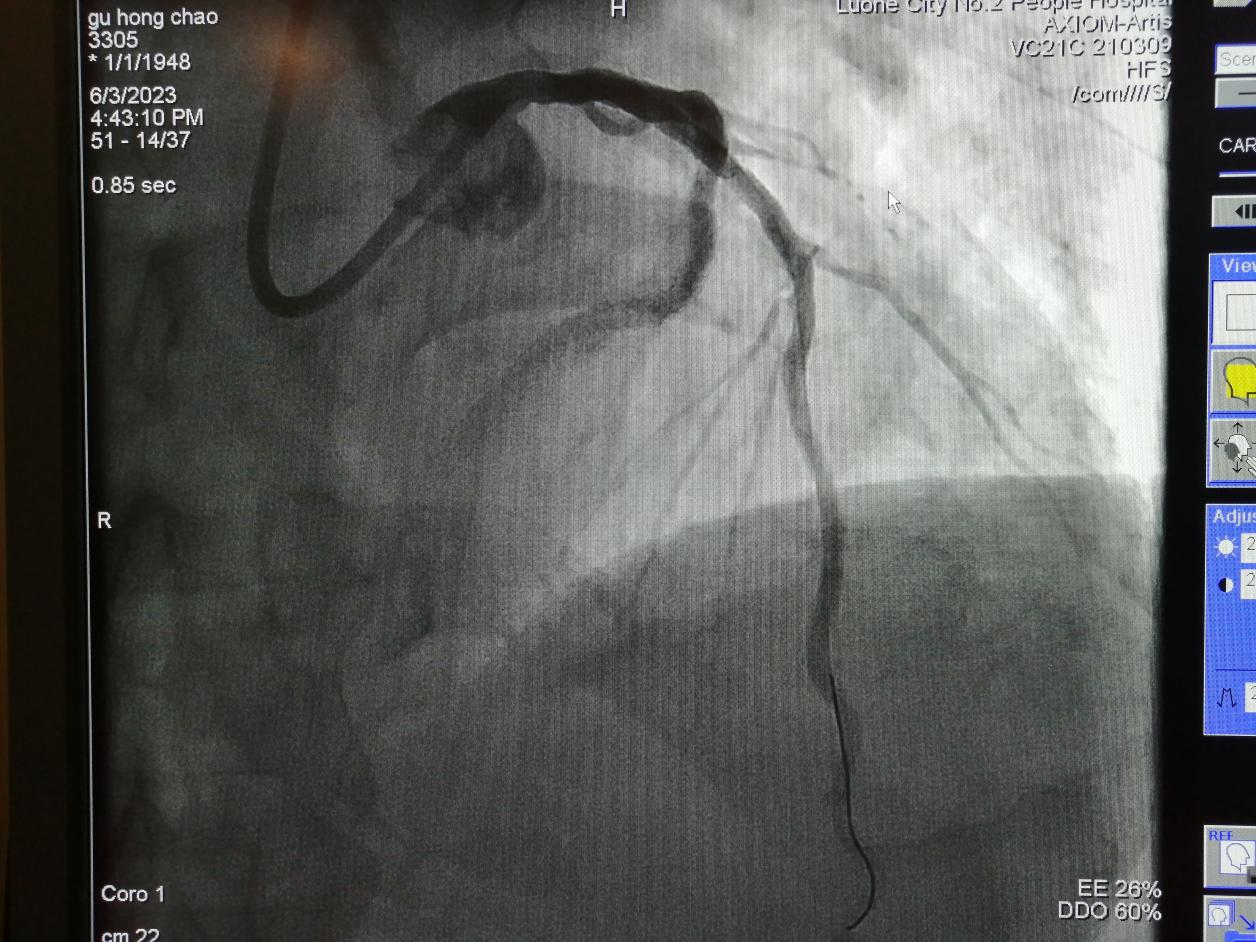

病例三

75歲的谷大爺,4年前行冠脈介入手術(shù)。近日,因“胸痛5天”入住心血管內(nèi)科,經(jīng)檢查冠脈造影發(fā)現(xiàn),前降支長段狹窄合并鈣化。

金叔宣教授帶領(lǐng)心血管內(nèi)科介入團(tuán)隊(duì)為谷大爺制定了個(gè)體化的手術(shù)治療方案,即行血管內(nèi)超聲,旋磨前降支,后置入心臟支架1枚。

術(shù)后,谷大爺胸痛癥狀得到有效緩解。

術(shù)后: